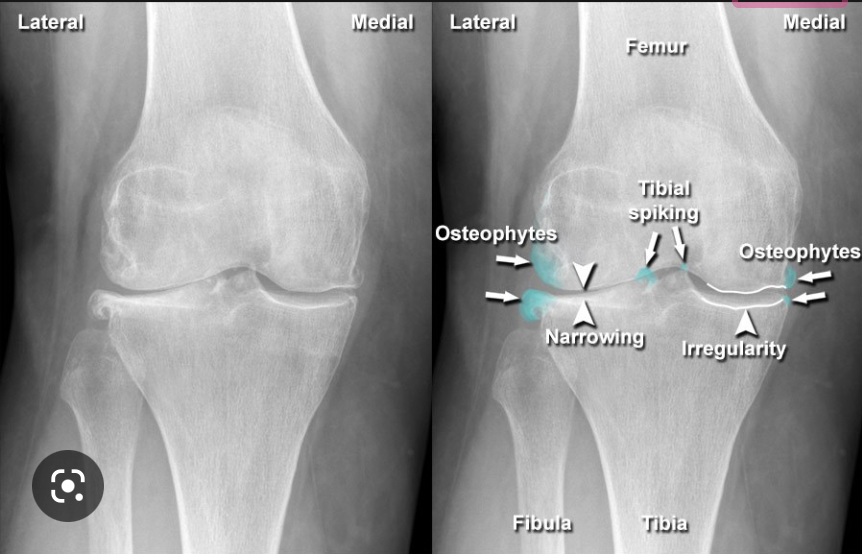

What mnemonic is used to remember the 4 key XR changes in osteoarthritis?

LOSS

L - loss of joint space

O - osteophytes (bone spurs)

S - subchondral cysts (fluid-filled holes in the bone)

S - subarticular sclerosis (increased density of bone along the joint line)